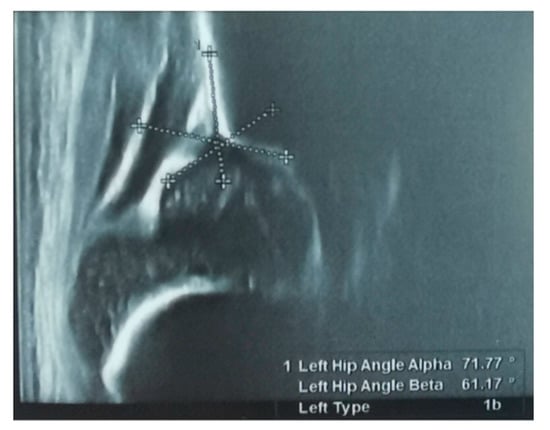

The screening was carried out by pediatric orthopedic physicians with training in Graf ultrasound hip screening for the developmental dysplasia of the hip. The measurement technique used was that according to the Graf criteria, and was used to determine the type of DDH [9], as seen in Figure 3.

Figure 3. Ultrasound measurements on a left hip ultrasound according to Graf ultrasound technique for the screening of development dysplasia of the hip. Image showing a Graf type 1b hip. From our collection of medical photos.

Graf has established the criteria for a normal hip on static ultrasonographic images as follows: a normal alpha angle value of over 60° between the bony acetabulum and the ilium and a beta angle less than 55° measured between the labrum and the turning point from convexity to concavity on the bony rim [8].